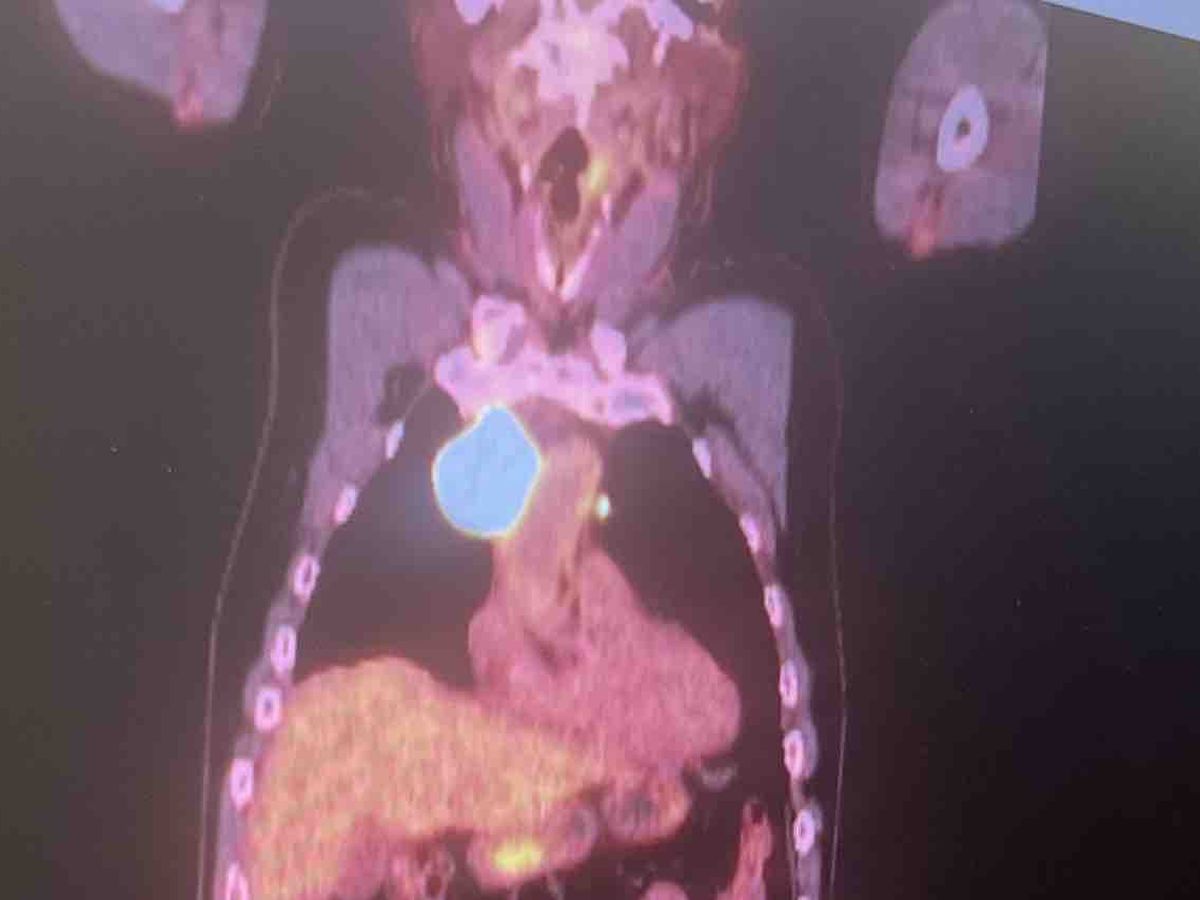

Hola me llamo Noylen J Pino soy la hija de Noel Pino operador de la compañía de Mastec en Miami y he creado este recaudación para mi papá debido a que empieza un tratamiento de quimioterapia por causa de su enfermedad de Linfoma de células B grandes donde ya tiene una masa de más de 5 cm atrás del corazón y ya también alcanzó la garganta.